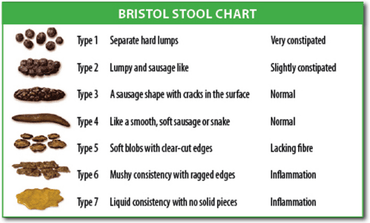

The diagnosis is essentially made from the patient's description of the symptoms. Bowel movements that are difficult to pass, very firm, or made up of small hard pellets (like those excreted by rabbits) qualify as constipation, even if they occur every day. Other symptoms related to constipation can include bloating, distension, abdominal pain, headaches, a feeling of fatigue and nervous exhaustion, or a sense of incomplete emptying.[23]